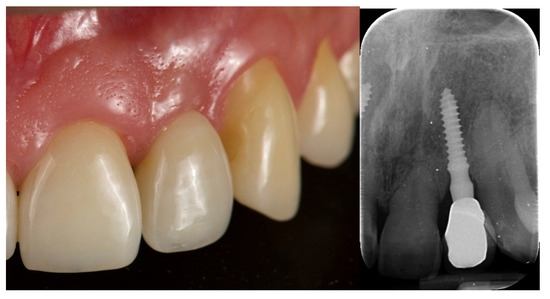

- Any biological complications (e.g., pain, swelling, mobility, suppuration) and/or technical issues (e.g., material fractures, screw loosening) were reported during follow-up;

- Esthetic evaluation of clinical pictures, including at least two adjacent teeth, taken at two years after loading was done following the pink esthetic score (PES) proposed by Fürhauser et al., in 2005 [31]. In brief, the PES score evaluates seven variables: mesial papilla, distal papilla, soft tissue level, soft tissue contour, alveolar process deficiencies, soft tissue color and texture. A 0-1-2 scoring system was used, with a maximum achievable score of 14 per site.

| PES 3 at the 2-year follow-up | 12.6 ± 0.97 | 12.2 ± 0.92 | 0.3554 |

| MBL4 at the 2-year follow-up | 0.23 ± 0.11 | 0.18 ± 0.12 | 0.3339 |